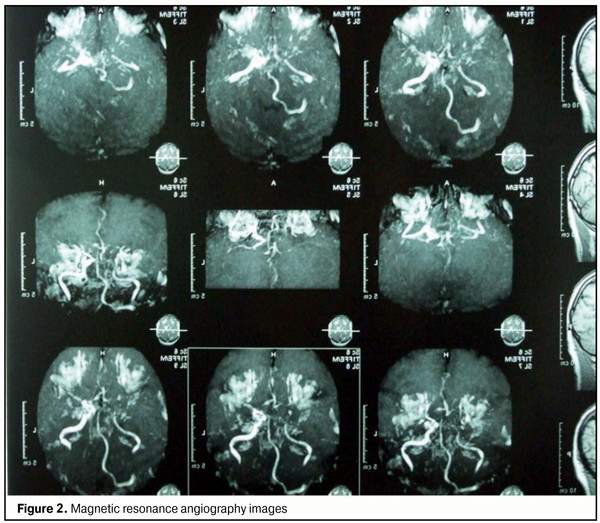

Findings of auxiliary clinical examinations: Complete blood count and urine examination were normal. The Duke's bleeding time was normal (210 s). EEG: the principal rhythm was sinus; heart rate, 62/min; no axis deviation; left ventricular hypertrophy. Findings of duplex Doppler sonography of carotid and cerebral vessels: The blood flow velocity in ophthalmic artery was substantially reduced on both sides. In addition, the size of the common carotid arteries was within the normal range, and the sonograms of common carotid arteries showed marked thickening (due to calcification) with inhomogeneous echogenicity. Multiple atherosclerotic plaques were visible in the right common and right internal carotid arteries. The blood flow velocity in the distal portion of the right internal carotid artery was reduced (distal stenosis). The diameter of the left vertebral artery was 3.4 mm, and there was no blood flow detected in the artery. The blood flow velocity in the internal carotid artery and in the right vertebral artery was reduced. The opinion formulated based on ultrasonography was as follows: ultrasonographic evidence of atherosclerotic disease involving brachiocerebral vessels. Brain MRI findings: A series of axial, saggital and frontal brain MRI images demonstrated no displacement of midline structures, no enlargement of the ventricular system, no changes in chiasmatic-sellar region, multiple intensive periventricular and subcortical foci, no changes in craniovertebral ligaments and in orbital coni, and free paranasal sinuses. Magnetic resonance angiography (MRA) demonstrated a poor vascular pattern, markedly reduced signal from the right carotid artery, elongated vertebral arteries, and reduced signal from the vertebral and communication arteries (more substantially, on the left). The opinion formulated based on brain MRI/MRA was as follows: discirculatory encephalopathy with marked manifestations of vertebrobasilar insufficiency (Fig. 2).